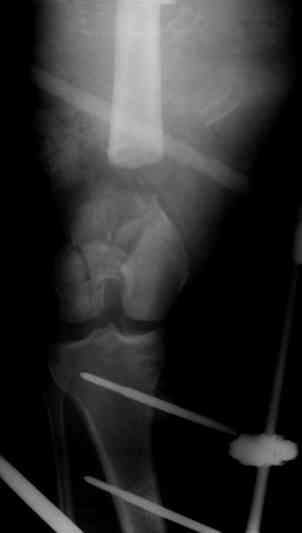

Если у Вас возникнут какие-то сомнения, то возможно наложение гибридного циркулярного-монолатерального дистракционного аппарата на левое бедро и выполнение остеотомии в в/3 бедра. Почему монолатеральный гибридный аппарат, а не аппарат Илизарова? Эта конструкция гораздо легче переносится пациентами, в ней гораздо удобнее проводить местное лечение ран.

Разрешите рассказать о пациенте, которому мы фиксировали перелом такой конструкцией.

Больной 19 ти лет, пострадал в результате ДТП, пассажир мотоцикла. Получил открытый оскольчатый перелом н/3 левой бедренной кости 3a тип по Гастилло-Андерсену. При поступлении ПХО ран, фиксация стержневым аппаратом наружной фиксации. Лечение больного осложнилось развитием анаэробной флегмоны левого бедра. Лампасные разрезы, неоднократные некрэктомии, некротизировался участок диафиза левой бедренной кости на протяжении 15 см. Произведена резекция. 20.05.10- демонтаж АНФ, остеоситез левой бедренной кости гибридным циркулярно-монолатеральным стержневым дистракционным аппаратом наружной фиксации, остетомия левой бедренной кости в в/3. Сейчас начата дистракция в аппарате, проводится подготовка ран к аутодермопастике.